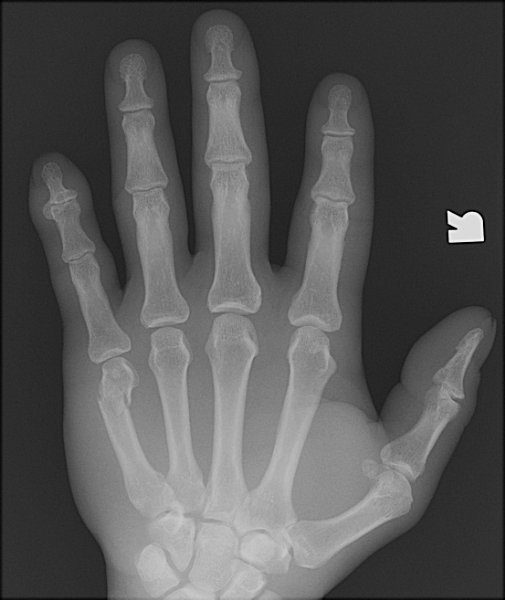

Return to Boxer's Fracture